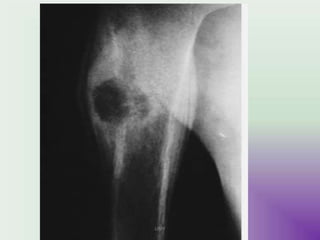

FIBROUS DYSPLASIA

UMY

-intrinsic defect of endochondral bone maturation  immature

ossification pattern

-Characterized by replacement of normal bone & marrow by

fibrous tissue & small woven spicules of bone  weakbone .

- Solitary or multifocal

- ALBRIGHT ‘ S SYN : polyostotic F.D + café au lait spots +

endocrinopathies .

- MAZABRAUD SYN- Polyostotic FD+ Intramuscular

myxomas

- Site : rib , femur , humerus , tibia , maxilla

- C.F : monostotic – asymptomatic

bone pain , skeletal

deformities .

RADIOGRAPHIC APPEARENCE

Radiographic features :

- Epiphysis or metaphysis or diaphysis

- Well defined geographic lytic lesions

- Ground glass matrix : intramedullary radiolucencies

- Cortical thinning

- Secondary deformities esp. in wt , bearing bones

- Shepherd’s crook deformity

( microfractures – on tension side of bone )

- Poorly defined areas of osteolysis

- Cortical destruction

- Soft tissue involvement

suspect

malignant

transformation

Shepherd's crook deformity

• Coxa varus angulation of the proximal femur,

classically seen in femoral involvement by fibrous

dysplasia, although may be seen in other disorders

such as Paget disese of bone and osteogenesis

imperfecta.

• The shape of the proximal femur resembles that of

the staff carried by herders (shepherds), which is

known as a crook.